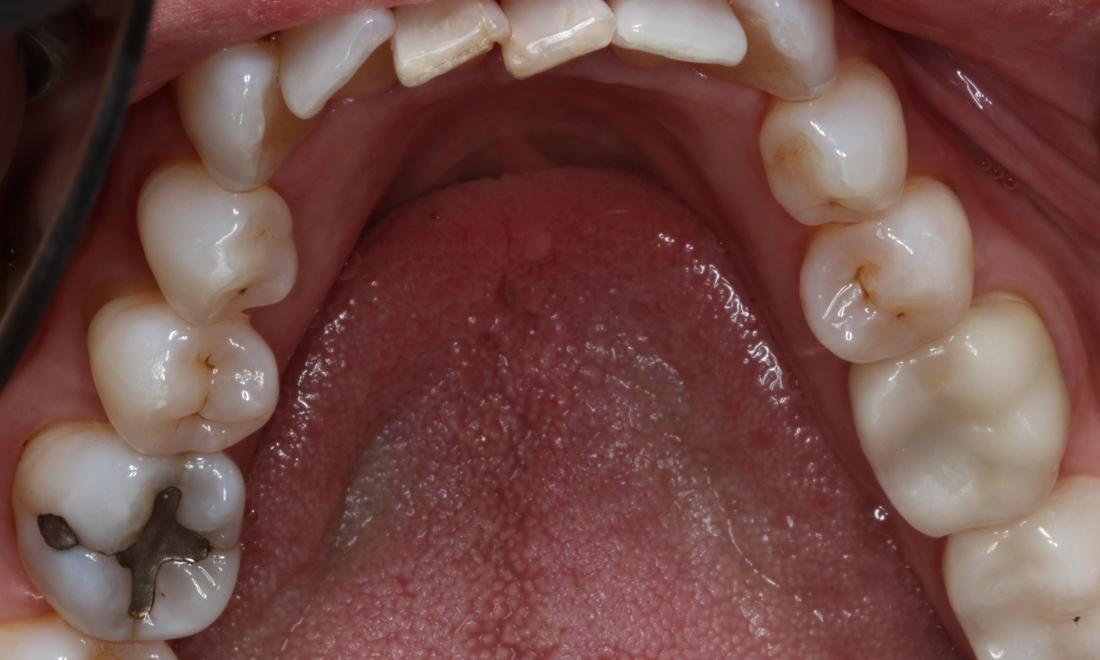

Patient before Lingual Tori Removal Patient after Lingual Tori treatment in Brentwood, TN